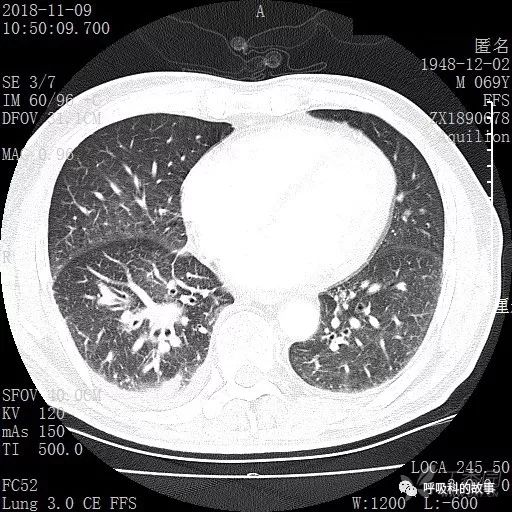

胸部增强CT示右肺门占位伴远端阻塞性肺炎,纵膈、右肺门、右侧颈根部、右侧腋下及肝门部肿大淋巴结。两侧胸腔少量积液。

肺窗CT

患者于2018年12月初又到了另一家大医院,做了PET检查和气管镜检查,PET图片和报告:右下肺病灶在增大,PET呈现高摄取率,SUV最大达11.